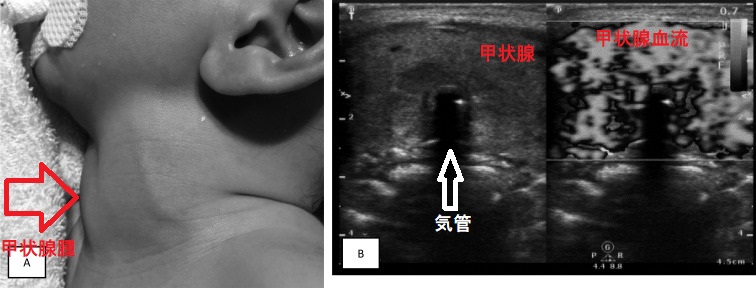

コントロール不良の甲状腺機能亢進症/バセドウ病母体から生まれた新生児バセドウ病の児で、巨大甲状腺腫による気道狭窄と新生児遷延性肺高血圧を来した報告があります(Clin Pediatr Endocrinol. 2018;27(3):171-178.)。

写真;新生児バセドウ病、巨大甲状腺腫による気道狭窄と新生児遷延性肺高血圧(BMJ Case Rep. 2012 May 30;2012:bcr0220125939.)